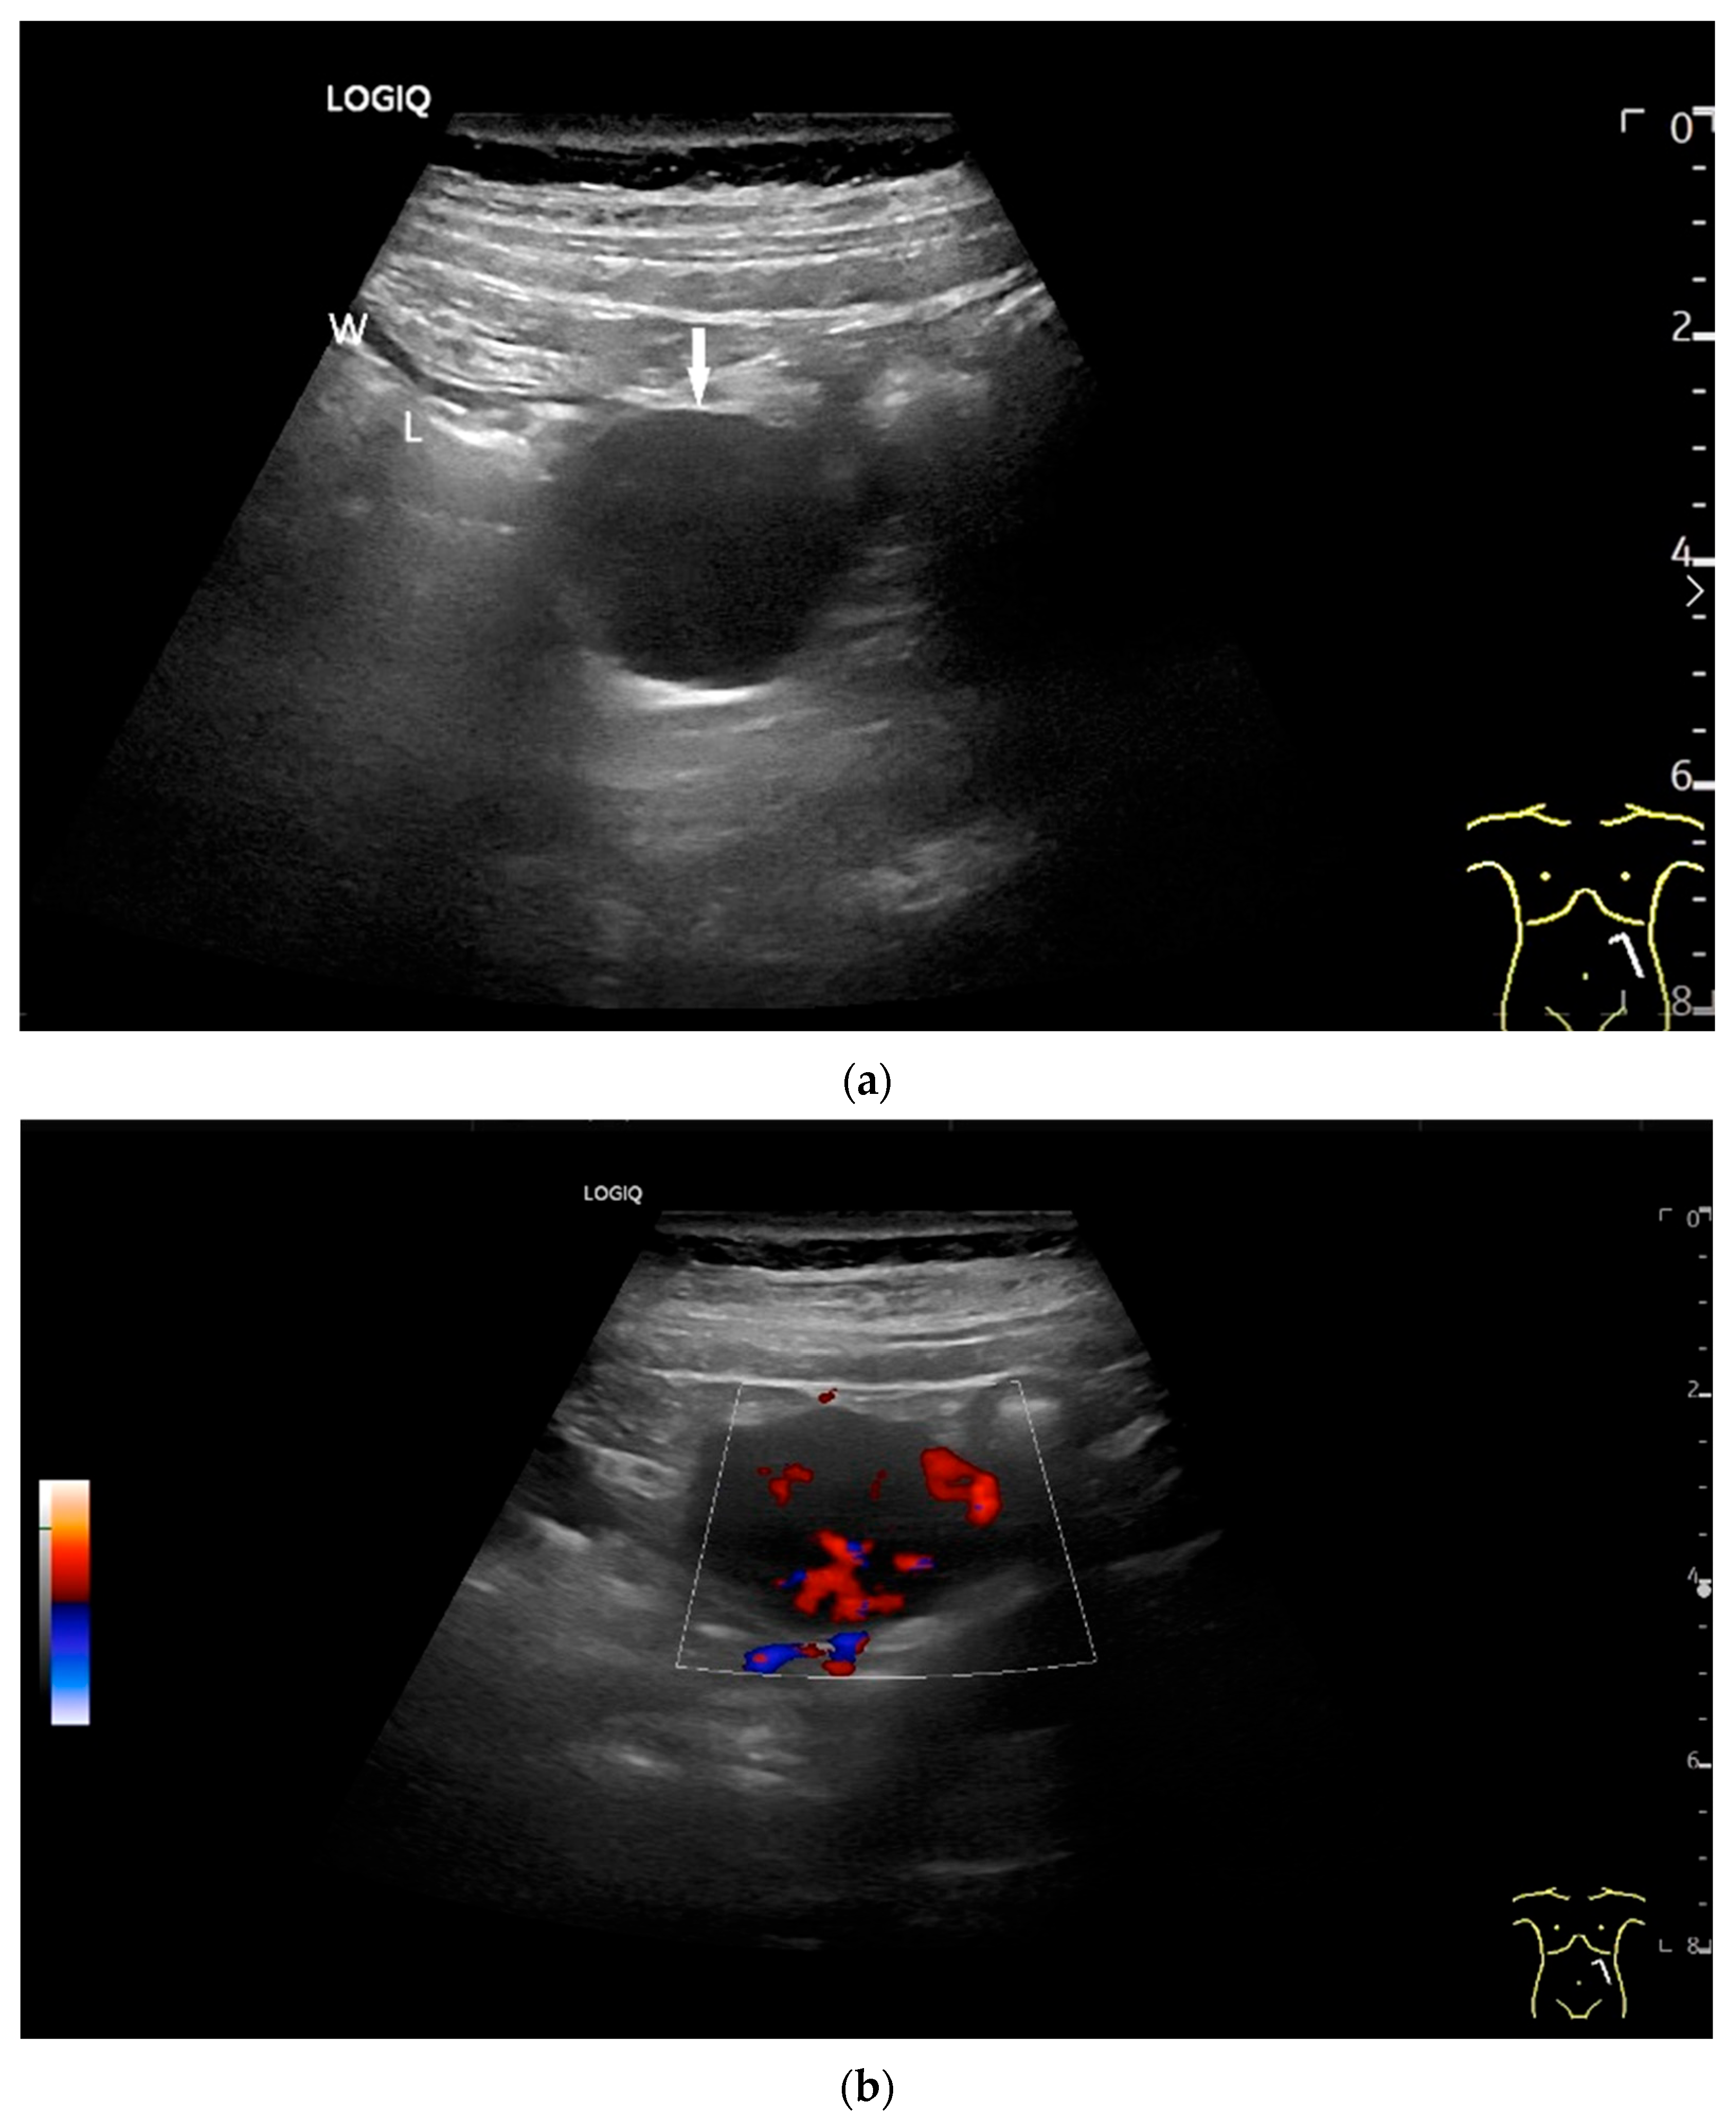

- Rispo, A.; De Sire, R.; D’Armiento, M.; De Bonis, L.; Tropeano, F.P.; Ricciolino, S.; Nardone, G.; Luglio, G. Ultrasonographic diagnosis of ileo-ileal intussusception secondary to Vanek’s tumor. Eur. Rev. Med. Pharmacol. Sci. 2022, 26, 350–353. [Google Scholar] [CrossRef]

| Neuroendocrine tumor | Small, nodular hypoechoic wall thickenings, mostly in the submucosa with spreading into the other layers. Usually with small vessels on CDI. Regionally enlarged lymph nodes. Multilocular manifestations are possible. |

| Lymphoma | Very pronounced wall thickening with marked hypoechogenicity. Large regional and distant lymph nodes. Look for splenic infiltration. Tumor vessels on CDI and hyperenhancement on CEUS. Heterogeneous hyperechogenicity of the mesentery with walling of the mesenteric vessels. Multiple localizations are possible. |

| GIST | Round hypoechoic masses, homogeneous or heterogeneous depending on size. They usually originate from the muscularis propria, which can be difficult to distinguish in US. Small vessels on CDI, hyperenhancement on CEUS. They move with the small intestine and can change position. |